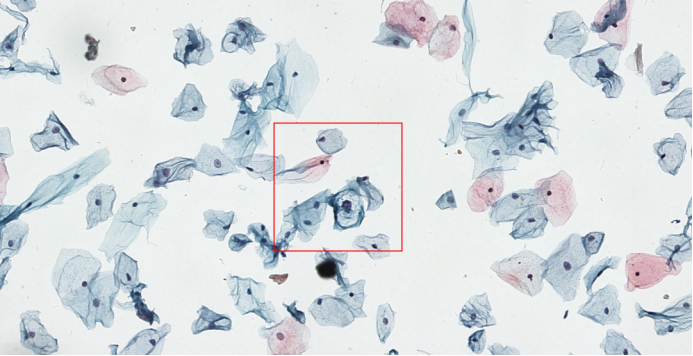

image.png

▲ 低度鳞状上皮内病变细胞(LSIL)